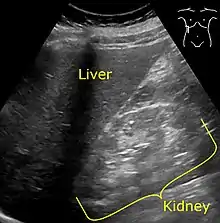

It is recommended that diabetics have their albumin levels checked annually, beginning immediately after a diagnosis of type 2 diabetes and five years after a diagnosis of type 1 diabetes.[27][30] Medical imaging of the kidneys, generally by ultrasonography, is recommended as part of a differential diagnosis if there is suspicion of urinary tract obstruction, urinary tract infection, kidney stones or polycystic kidney disease.[31] Conformation kidney biopsy should only be performed if non-diabetic kidney disease is suspected.